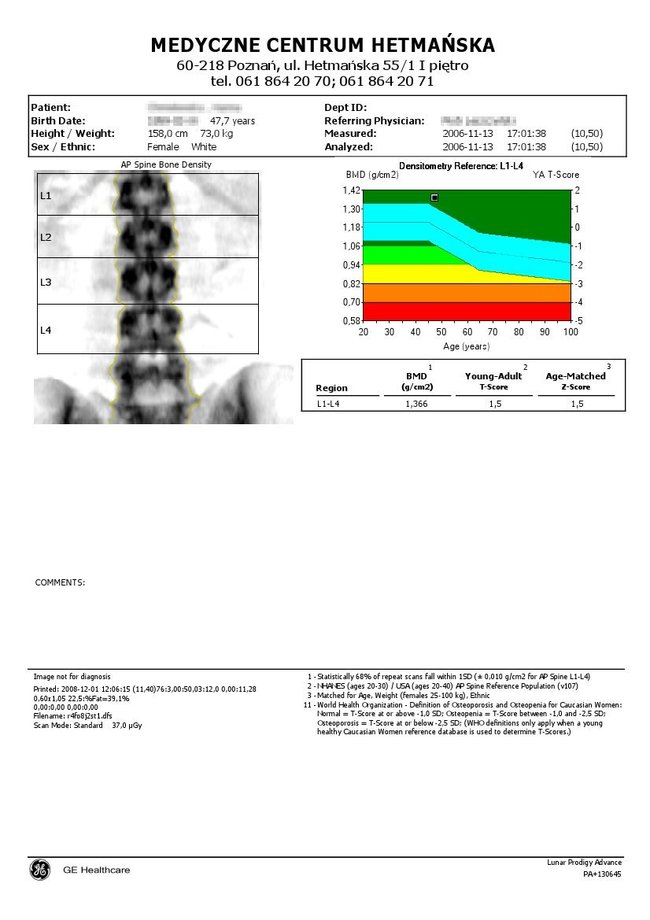

Wynik przedstawiony jest w formie wykresu i tabeli i podawany w g/cm2.

DENSYTOMETRIA KRĘGOSŁUPA LĘDŹWIOWEGO Standardowo zaleca się wykonywanie takich oznaczeń co 12 miesięcy, na tym samym aparacie , w tej samej lokalizacji oraz najlepiej przy tej samej osobie obsługującej urządzenie (najmniejszy błąd pomiarowy).

Wg zaleceń Międzynarodowego Stowarzyszenia Densytometrii Klinicznej (ang. International Society for Clinical Densytometry) z roku 2007 pomiar gęstości mineralnej kości (ang. BMD – Bone Mineral Density) kręgosłupa lędźwiowego L1 – L4 jest zalecany do łącznej oceny z wynikami morfometrycznym metodą DXA (VFA ang. Vertebral Fracture Assessment) oraz oceną klinicznych czynników ryzyka złamań. |

Podczas badania przeprowadzanego w pozycji leżącej na plecach zostaje wykonany pomiar gęstości mineralnej kości (ang. BMD – Bone Mineral Density) kręgosłupa lędźwiowego L1 – L4. W przypadku pomiarów kolejnych aparat LUNAR PRODIGY ADVANCE z oprogramowaniem enCORE porównuje procentowo wyniki z poprzednimi oznaczeniami i umiejscawia je na wydruku, który otrzymuje pacjent.

Badanie zostaje wykonane przy niskich względem klasycznej metody RTG dawkach promieniowania jonizującego. Jest więc bezpieczniejsze i mniej szkodliwe oraz istnieje możliwości ponownego badania w krótkim czasie. Poza tym zastosowanie najnowszych rozwiązań technologicznych gwarantuje wysoką jakość obrazu oraz standaryzowaną procedurę pomiaru.